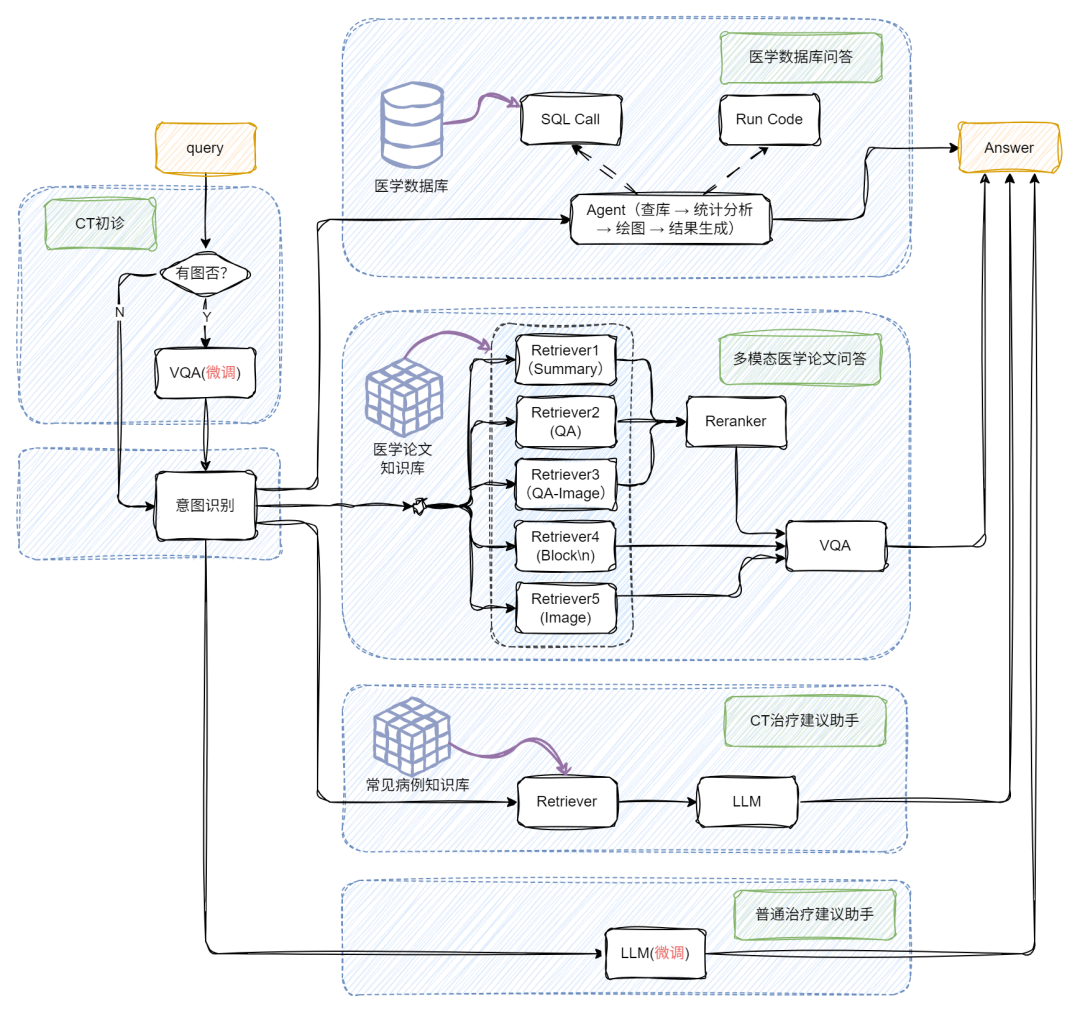

下图和视频效果是我们今天的目标!涉及多路召回多模态RAG、多模态问答、Chat-BI、Agent、LLM微调、多模态模型微调等等。让我们开始吧!

通过前面的探索,我们已经了解了朴素 RAG 如何让大模型具备“查资料再回答”的基础能力,也见证了多模态 RAG 通过图文融合实现的“感官升级”。但当实际应用场景涉及“医院年度病例统计分析”、“科研文献数据可视化呈现”等需求时,单纯的多模态处理仍显不足 —— 这类场景既需要解析医学影像、病历文本等非结构化数据,又要对接数据库完成指标计算、图表生成等 BI任务。

如何让 RAG 系统同时驾驭多模态理解与结构化数据分析?接下来要展开的多模态 + BI复杂架构实战,正是为解决这类“既要又要”的高阶需求而生,我们将在朴素 RAG 基础上层层叠加关键模块,最终打造出能同时处理影像诊断、数据统计、图表生成的全能型 AI 助手!

首先登场的是

VQA 模块(Visual Question Answering)

👇

当用户提问中包含图片时,系统会自动触发 VQA,对图像进行结构化信息提取,挖掘上下文关键内容;若没有图像,就跳过这步,直接进入文本处理环节,效率UPUP!

接下来,系统通过意图识别模块,将不同类型的问题智能分流:

📌论文问答? 走传统 RAG 路线!向量检索+大模型生成,精准提取相关文献内容。

📌统计问答? 开启 SQL 模式!从提问中抽取结构化信息(如指标、维度、过滤条件),自动生成 SQL 查询,查询结果再由大模型“翻译”成自然语言,一目了然!

6 多模态 + BI + 医疗落地:

打造懂医学的 RAG 系统

基于前面多模态与 BI 能力的深度融合实践,我们进一步将 RAG 系统向医疗垂直场景做了进阶升级 —— 如今这套架构不仅能处理常规的文本问诊,更能通过 VQA 模块与医学知识库的联动,实现 CT 影像解析与智能诊断辅助的核心能力,打通了从临床咨询到辅助决策的全流程服务闭环。下面就带大家看看这套融合多模态理解、数据统计与专业知识的医疗 RAG 系统是如何落地的!

主要实现代码如下:

def build_paper_assistant():llm = OnlineChatModule(source='qwen', stream=False)with pipeline() as ppl:ppl.ifvqa = lazyllm.ifs(lambda x: x.startswith('<lazyllm-query>'),vqa_ppl, lambda x:x)with IntentClassifier(llm) as ppl.ic:ppl.ic.case["论文问答", paper_ppl]ppl.ic.case["统计问答", sql_ppl]ppl.ic.case["普通医疗问诊", inquiry_ppl]ppl.ic.case["CT医疗问诊", ct_ppl]return ppl